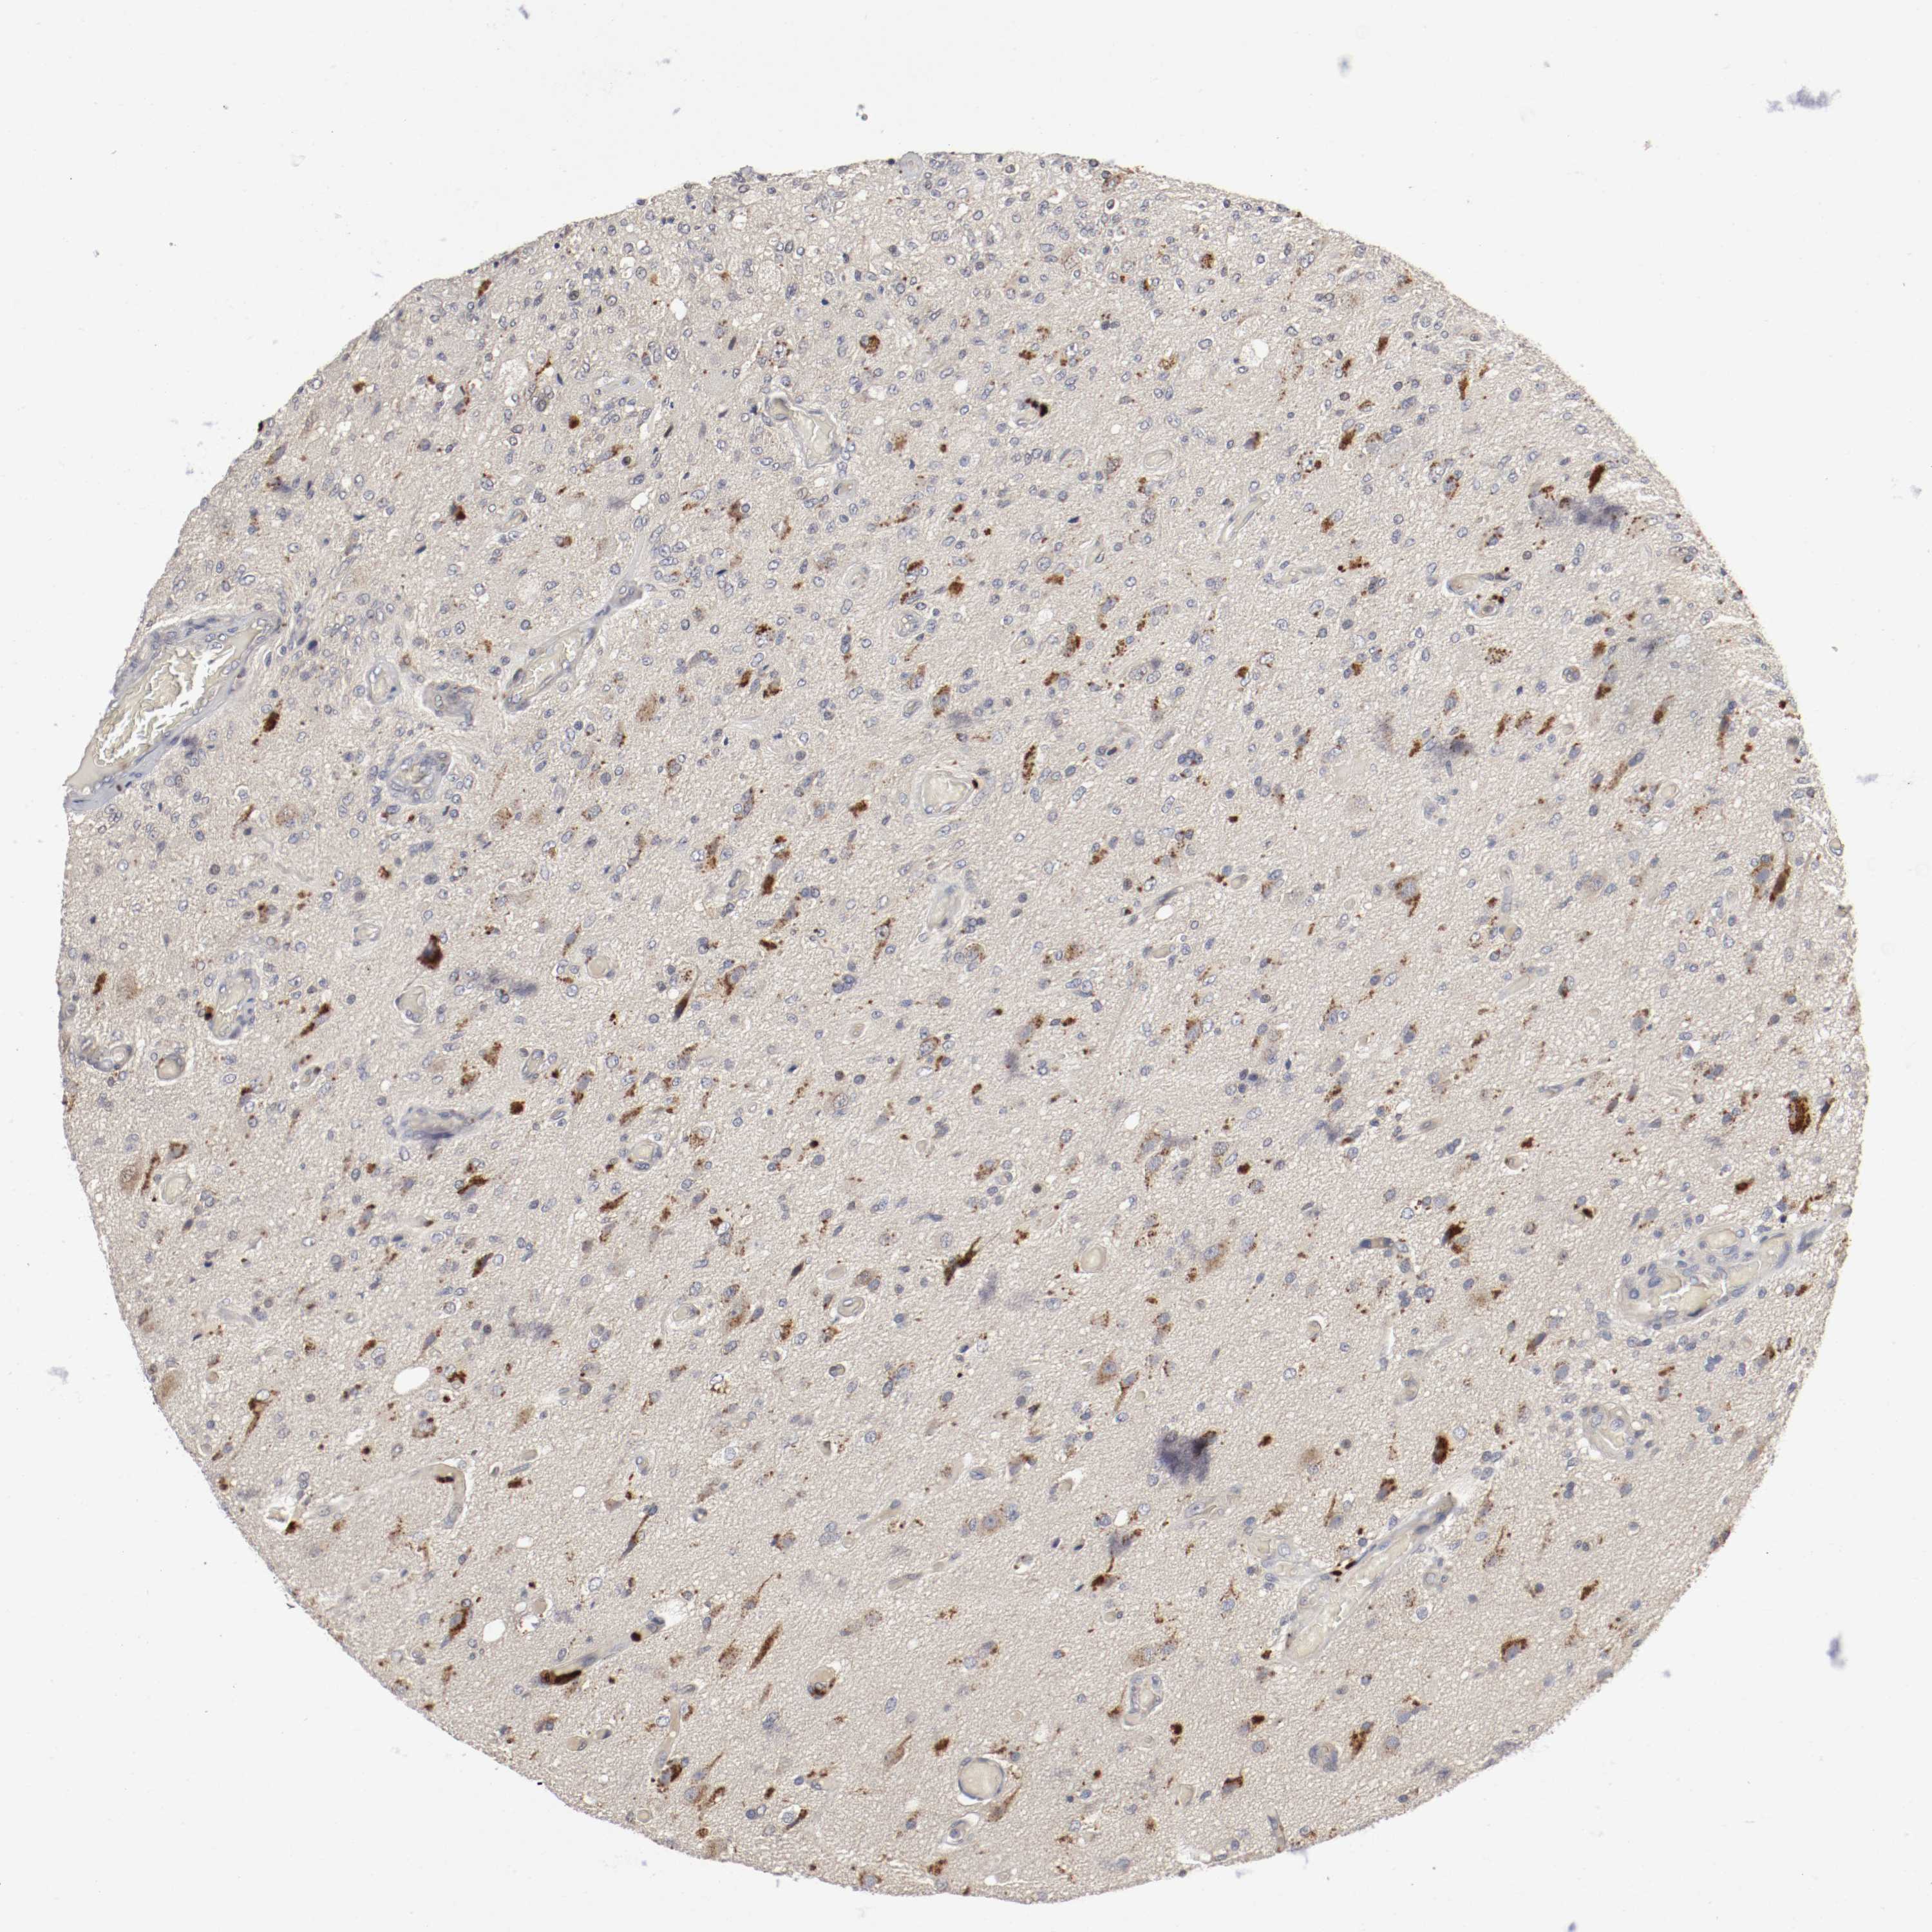

GLIOMA - Protein expressioni

A mouse-over function shows sample information and annotation data. Click on an image to view it in a full screen mode. Samples can be filtered based on level of antibody staining by selecting one or several of the following categories: high, medium, low and not detected. The assay and annotation is described here.

Antibody stainingi

Antibody staining in the annotated cell types in the current human tissue is reported as not detected, low, medium, or high, based on conventional immunohistochemistry profiling in selected tissues. This score is based on the combination of the staining intensity and fraction of stained cells.

Each image is clickable and will lead to virtual microscopy that enables deeper exploration of all samples and also displays staining intensity scores, fraction scores and subcellular localization as well as patient and tissue information for each sample.

Antibody HPA005131

Staining

High

Medium

Low

Not detected

Intensity

Strong

Moderate

Weak

Negative

Quantity

>75%

75%-25%

<25%

None

Location

Nuclear

Cytoplasmic/membranous

Cytoplasmic/membranous,nuclear

Glioma, malignant, High grade

Glioma, malignant, NOS

Glioma, malignant, Low grade